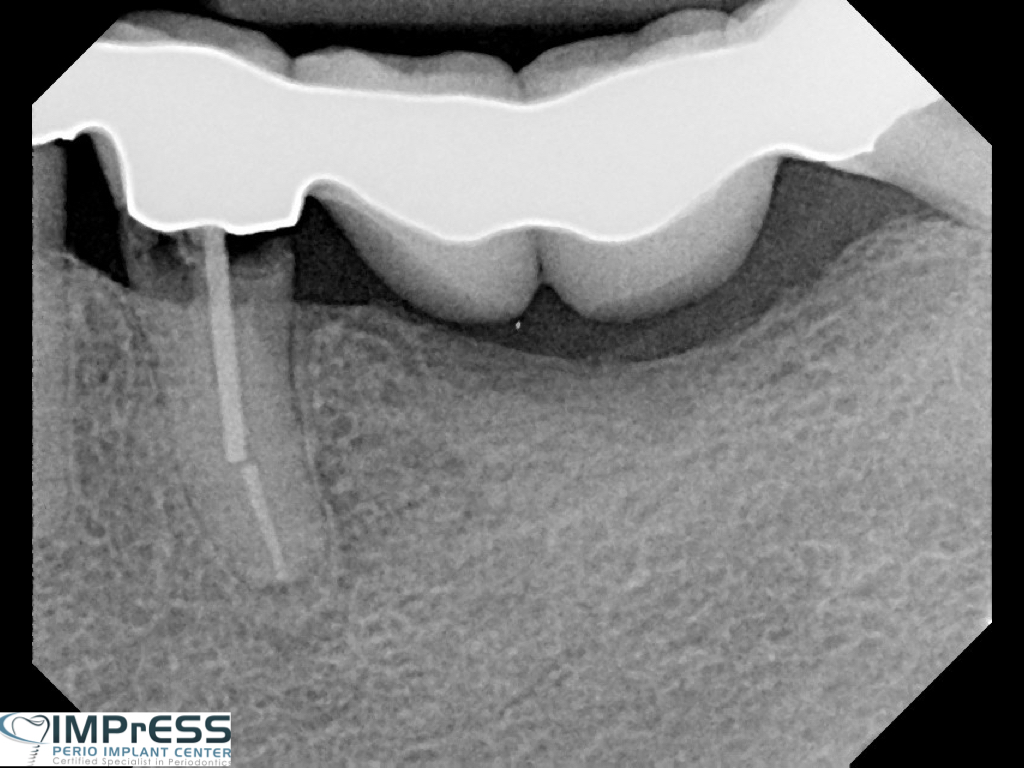

Guided Tissue Regeneration with Bone Graft & Growth Factors to Save teeth